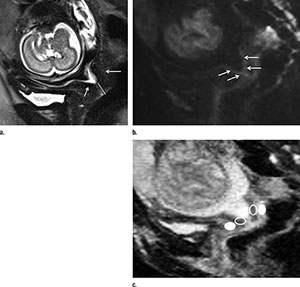

To learn more, Dr. Masselli and colleagues used an MRI technique called diffusion-weighted imaging (DWI) to examine pregnant women who had been referred for suspected fetal or placental abnormality. DWI reveals differences in the mobility of water molecules in tissue and the results can be used to create apparent diffusion coefficient (ADC) maps that provide a measure of local cell density. DWI has been increasingly used for abdominal and pelvic diseases, but has not been tested for the evaluation of the uterine cervix in pregnant patients.

Of the 30 women, eight, or 27 percent, delivered within a week of the MRI examination. The other 22 delivered an average of 55 days later. The researchers compared differences in ADC values at MRI between two areas of the cervix: the inner, subglandular zone and the outer, stromal area. While stromal ADC and sonographic cervical length showed no difference between both groups, the subglandular ADC was higher in patients with impending delivery, suggesting an increased mobility of water molecules in that area consistent with cervical ripening.

"Our results indicate that a high ADC value recorded at the level of the subglandular area of the cervix is associated with the imminent delivery of asymptomatic patients with a short cervix," Dr. Masselli said. "In detail, the subglandular ADC was inversely correlated to the time interval between MRI and delivery and therefore emerged as a powerful imaging biomarker in evaluating patients with impending delivery."